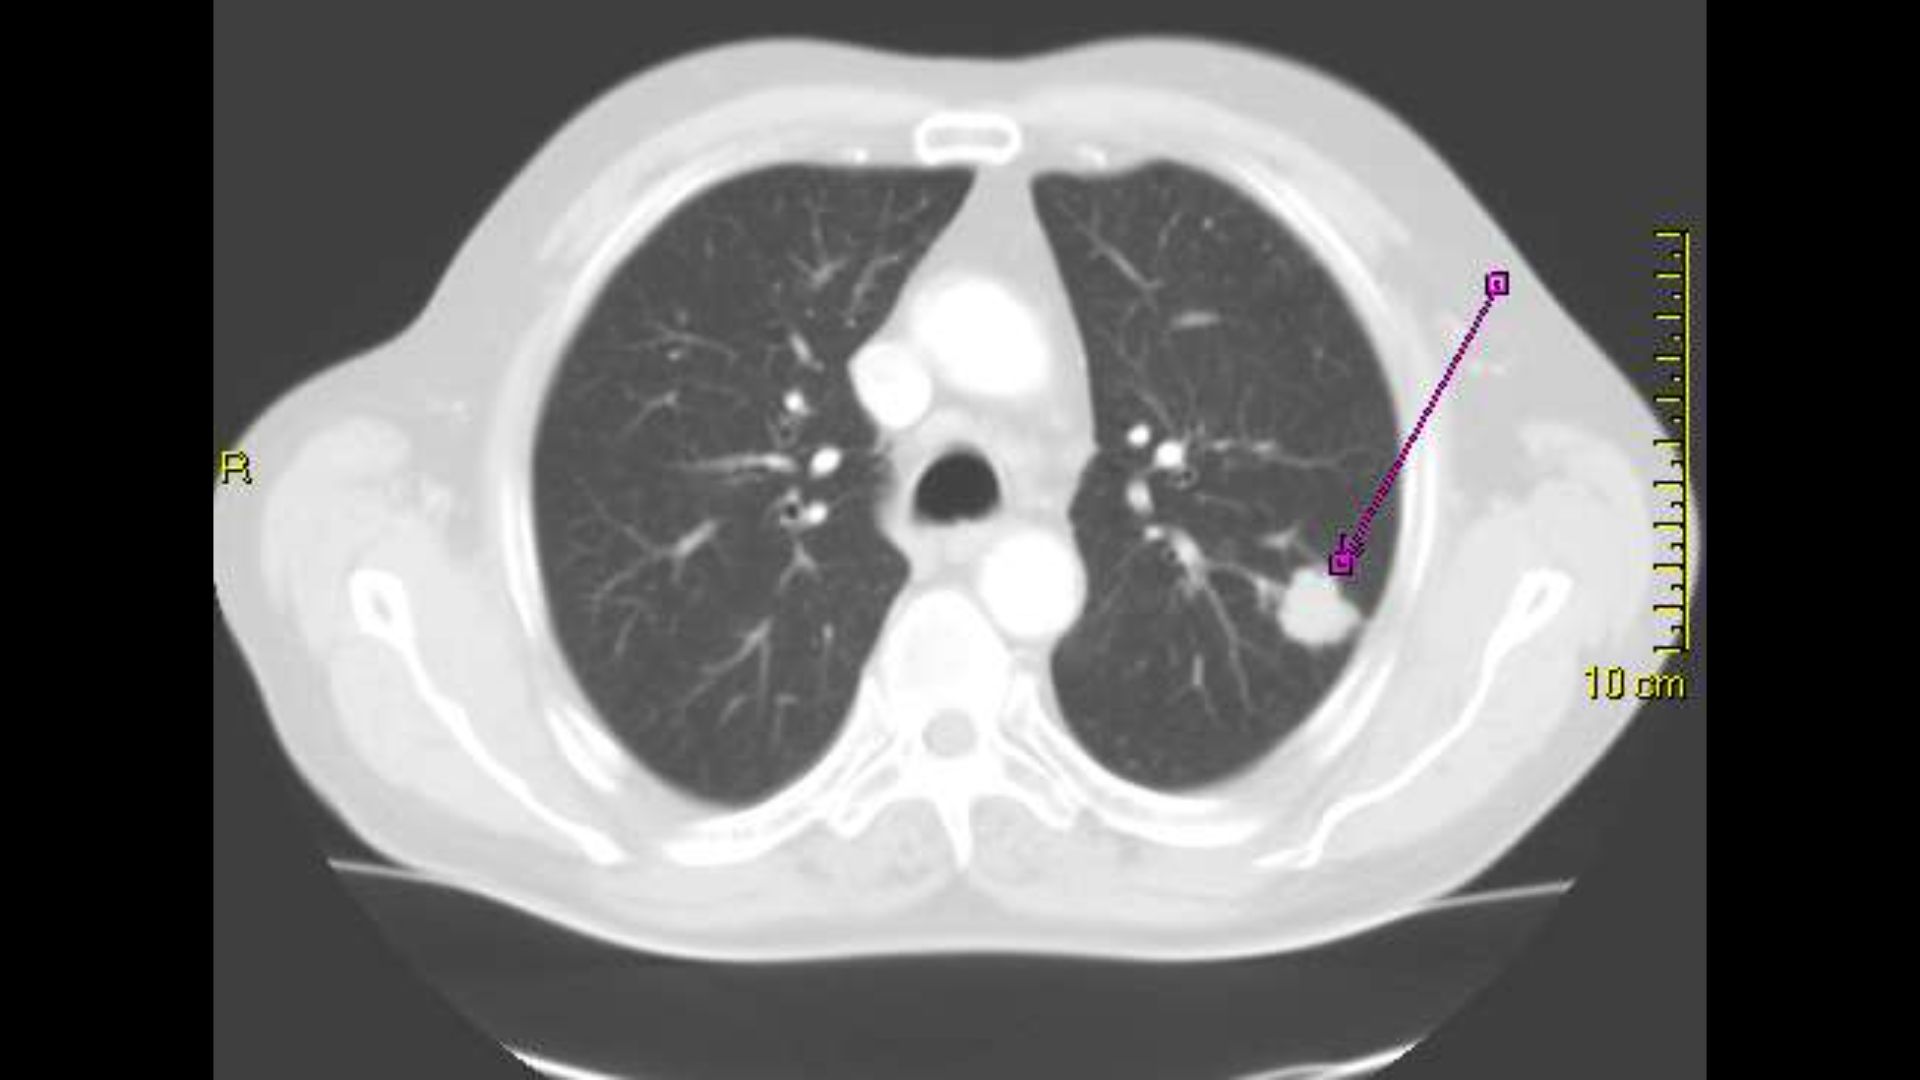

Diagnostik > Bildgebung

Rundherd: Wahrscheinlichkeit für Malignität ↗ bei > 40-Jährigen und Rauchern

Die Wahrscheinlichkeit, dass einem Lungenrundherd im Röntgen-Thx etwas Malignes zugrunde liegt, ist deutlich höher bei über 40-Jährigen und Rauchern.

Röntgen Rundherd → unscharfe Begrenzung

Gewisse Kriterien des Rundherdes deuten auf einen malignen Tumor hin.

Röntgen Rundherd → Tumorausläufer